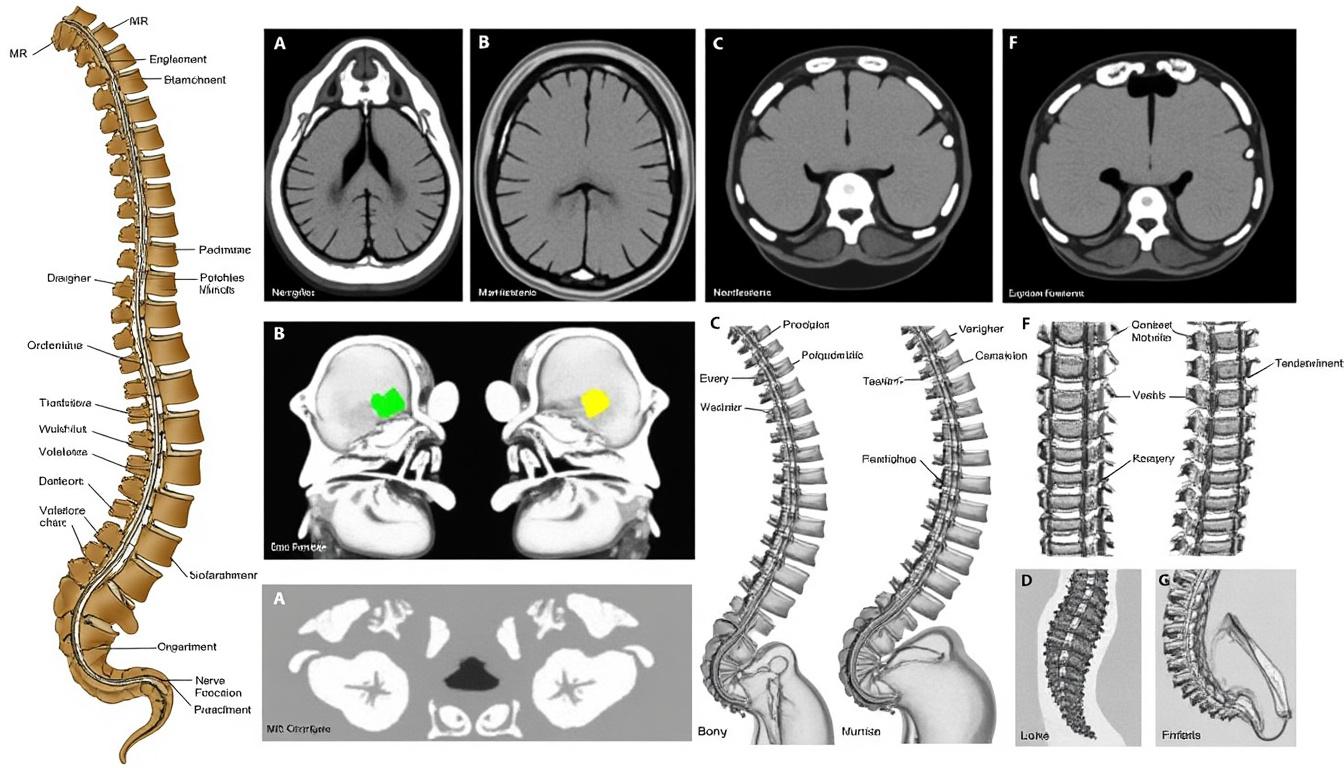

Determining medical eligibility for back surgery involves a thorough evaluation designed to ascertain whether surgical intervention will yield benefits that outweigh associated risks. This assessment is grounded in a detailed review of the patient’s spinal pathology, symptom severity, and prior treatment responses. For example, imaging techniques such as MRI and CT scans play an essential role in confirming diagnoses ranging from herniated discs to spinal canal stenosis or complex deformities like scoliosis and spondylolisthesis. These diagnostic insights inform the surgical approach, whether it be decompression, fusion, or dynamic stabilization.

- Radiological Evidence: Confirmed findings like nerve compression, disc degeneration, or vertebral instability guide decision-making.